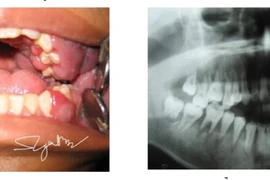

Bệnh nhi đầu tiên được ghép tế bào gốc

ANTĐ - Viện Huyết học - Truyền máu Trung ương vừa công bố ca ghép tế bào gốc tạo máu đồng loại cho bệnh nhi đầu tiên được điều trị thành công tại Viện bằng phương pháp này.